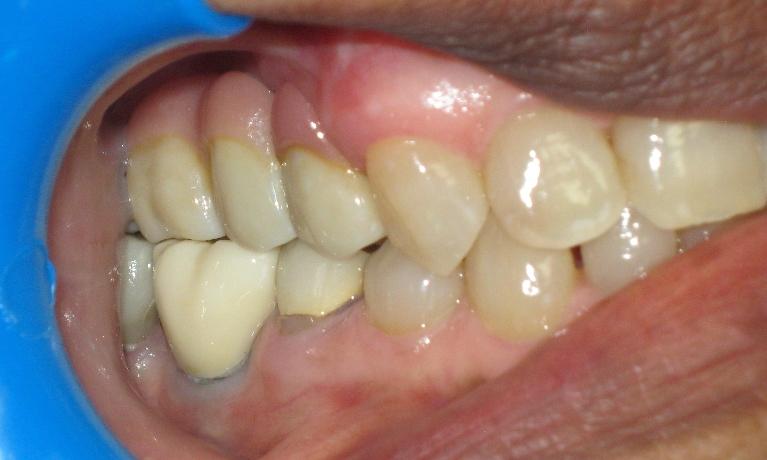

We take great pride in the services we perform in our office. We always try to not only meet your expectations, but we also try to exceed them. There are many types of services that we perform in our office, as well as others that we perform in coordination with highly skilled specialists. We have compiled a few examples of the treatments that we have performed. We are proud to say that these are the usual results our patients expect to see.

The photos are not retouched, nor are they taken by a professional photographer. These are just the routine treatment photos that we take and the results that we see every day. They are by no means a comprehensive catalog of the procedures that we perform. They are just a small sample of some of the results you can expect when you seek treatment in our office.